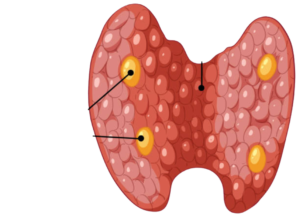

thyroid